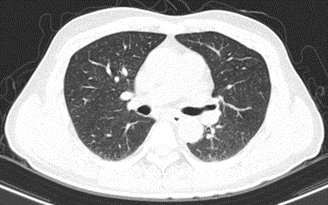

Hình 2: Hình ảnh chụp cắt lớp vi tính lồng ngực: Không thấy các tổn thương thứ phát